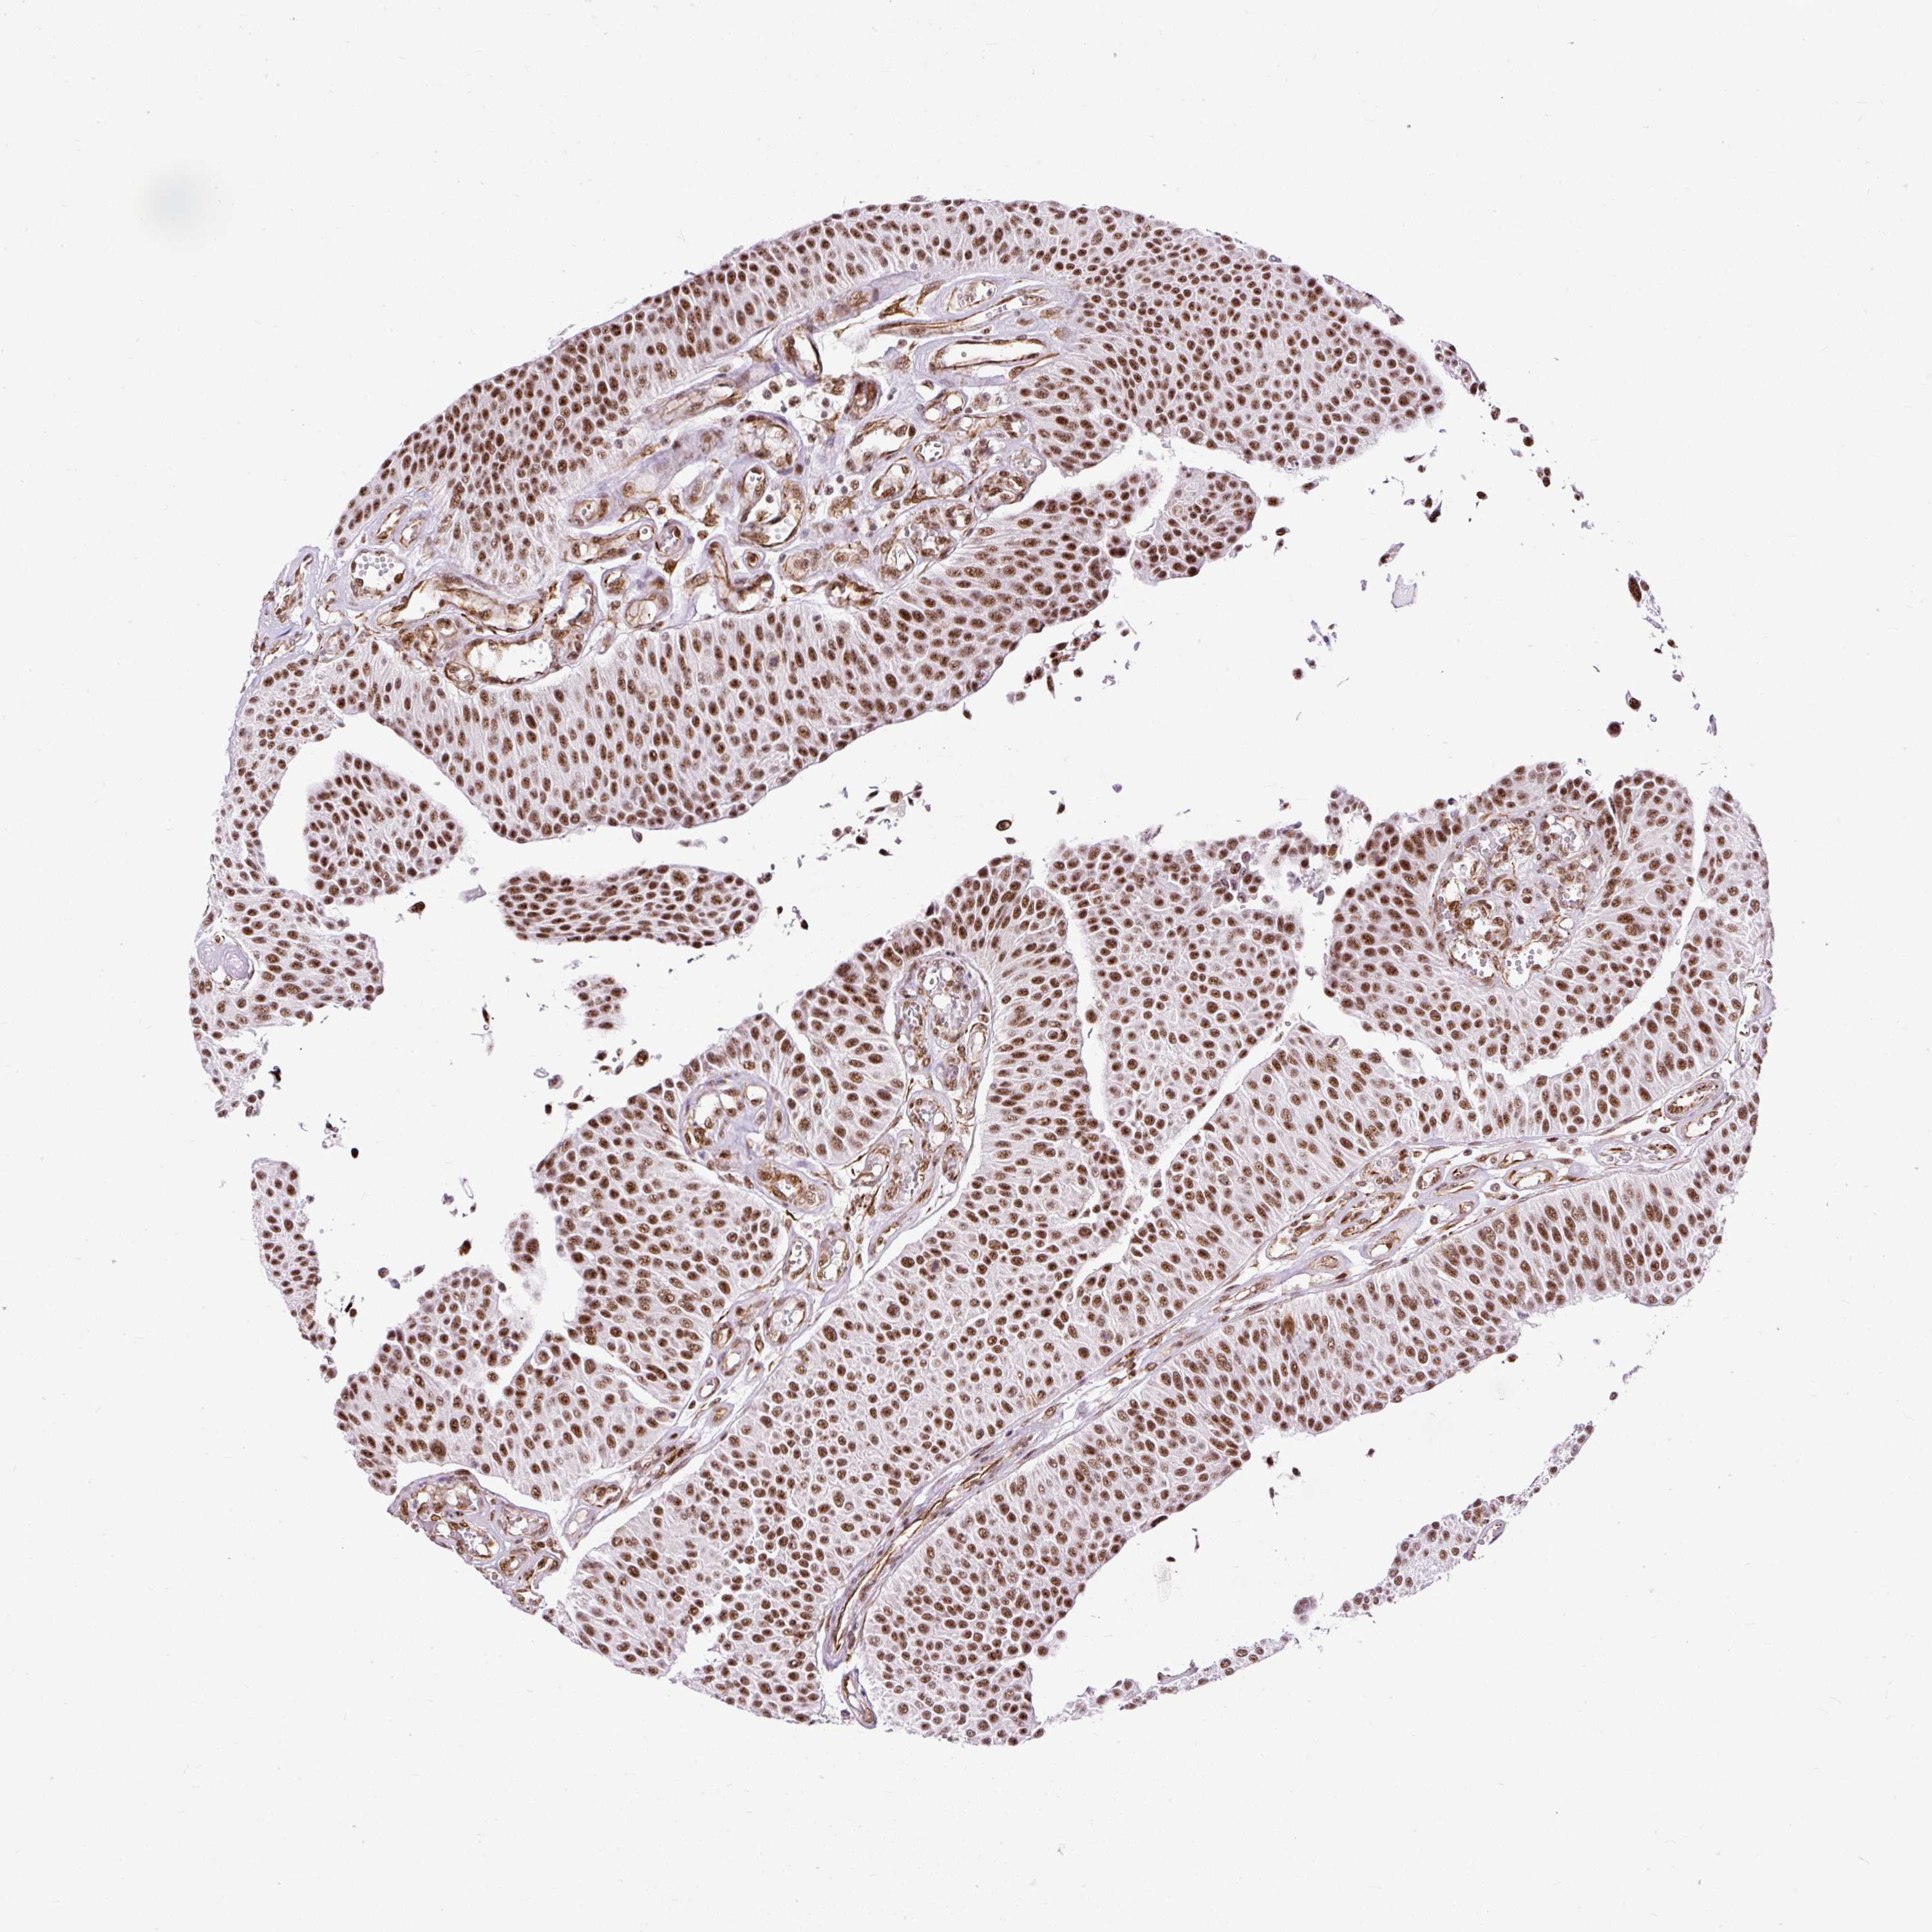

UROTHELIAL CANCER - Protein expressioni

A mouse-over function shows sample information and annotation data. Click on an image to view it in a full screen mode. Samples can be filtered based on level of antibody staining by selecting one or several of the following categories: high, medium, low and not detected. The assay and annotation is described here.

Antibody stainingi

Antibody staining in the annotated cell types in the current human tissue is reported as not detected, low, medium, or high, based on conventional immunohistochemistry profiling in selected tissues. This score is based on the combination of the staining intensity and fraction of stained cells.

Each image is clickable and will lead to virtual microscopy that enables deeper exploration of all samples and also displays staining intensity scores, fraction scores and subcellular localization as well as patient and tissue information for each sample.

Antibody HPA045663

Antibody HPA051631

Staining

High

Medium

Low

Not detected

Intensity

Strong

Moderate

Weak

Negative

Quantity

>75%

75%-25%

<25%

None

Location

Nuclear

Cytoplasmic/membranous

Cytoplasmic/membranous,nuclear

Urothelial carcinoma, High grade

Urothelial carcinoma, NOS

Urothelial carcinoma, Low grade